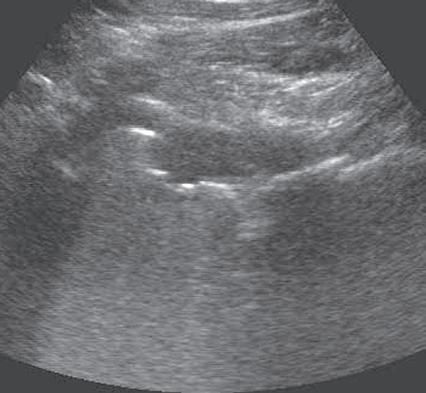

Another artifact with musculoskeletal implications is posterior reverberation. This occurs when the surface of an object is smooth and flat, such as a metal object or the surface of bone. In this situation, the sound beam reflects back and forth between the smooth surface and the transducer and produces a series of linear reflective echoes that extend deep to the structure.7 If the series of reflective echoes is more continuous deep to the structure, the term ring-down artifact is used, as may be seen with metal surfaces (Fig. 1.19). Ultrasound is ideal in evaluation of structures immediately overlying metal hardware because this reverberation artifact occurs deep to the hardware without obscuring the superficial soft tissues. Related to posterior reverberation is the

FIGURE 1.19 Ring-Down Artifact. Ultrasound image in long axis to the femoral component of a total hip arthroplasty shows the hyperechoic metal surface of the arthroplasty (arrows) and posterior ring-down artifact (open arrows). Note the overlying joint fluid (f) and adjacent native femur (F).